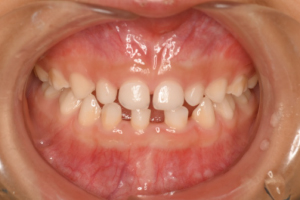

歯並びが気になる

レントゲン写真 治療内容・期間 7歳の時に、歯並びが気になるとのことでいらっしゃいました。最初の状態が左の写真です下の前歯は叢生です。上の前歯は、オレンジの矢印のところに側切歯が入るはずなのですが、隙間が小さくて出てこられない状態でした。さらにその後ろの犬歯も、顎の中で重なり合っていて出にくくなっています。 7歳の時...